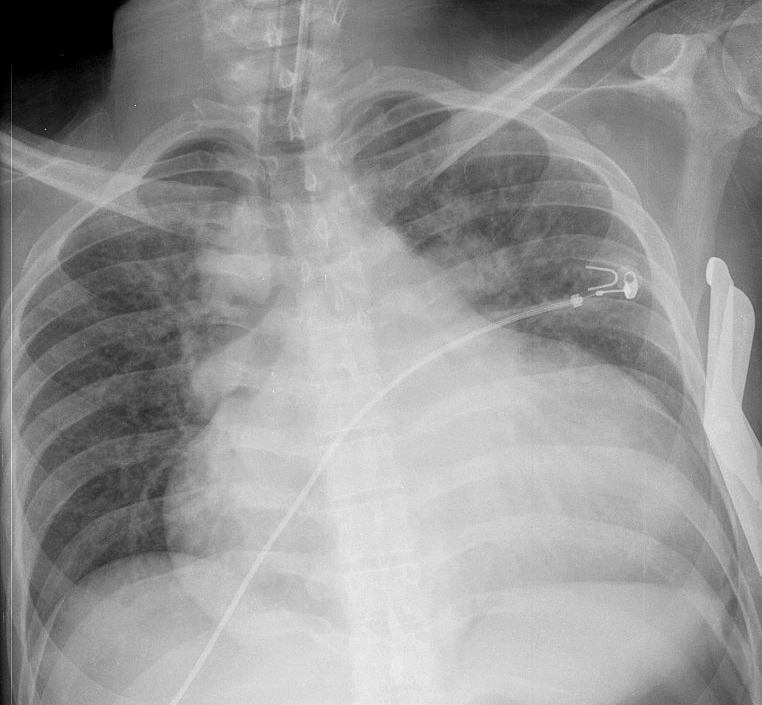

cardiomyopathy